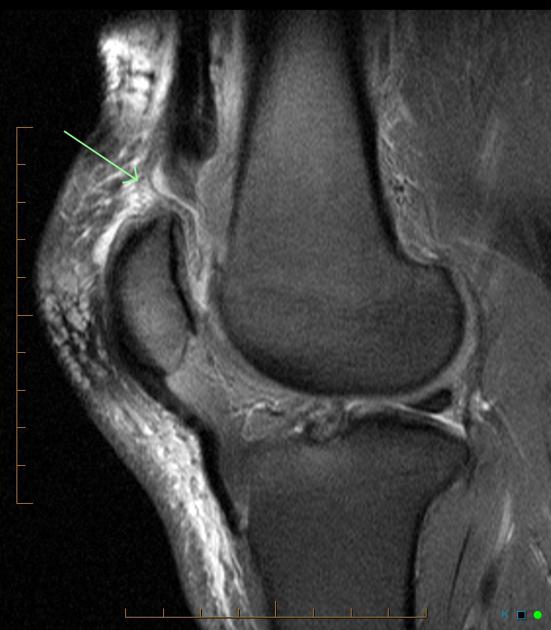

Ved tvivl laves akut MR-skanning, som altid kan vise læsionen.